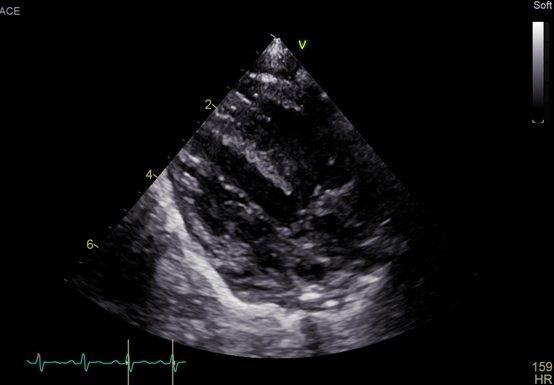

An echocardiogram showed a large ventricular septal defect overriding the aorta with septum and quadricuspid aortic valve (Figure). No stenosis or regurgitation was observed though the valve. The valve consisted of 3 equal cusps and a smaller one, which is type B according to the Hurwitz and Roberts classification (Video). Fluorescent in situ hybridization was negative for 22q11 deletion. The patient established feeds and was discharged home with the plan to have regular follow-ups.